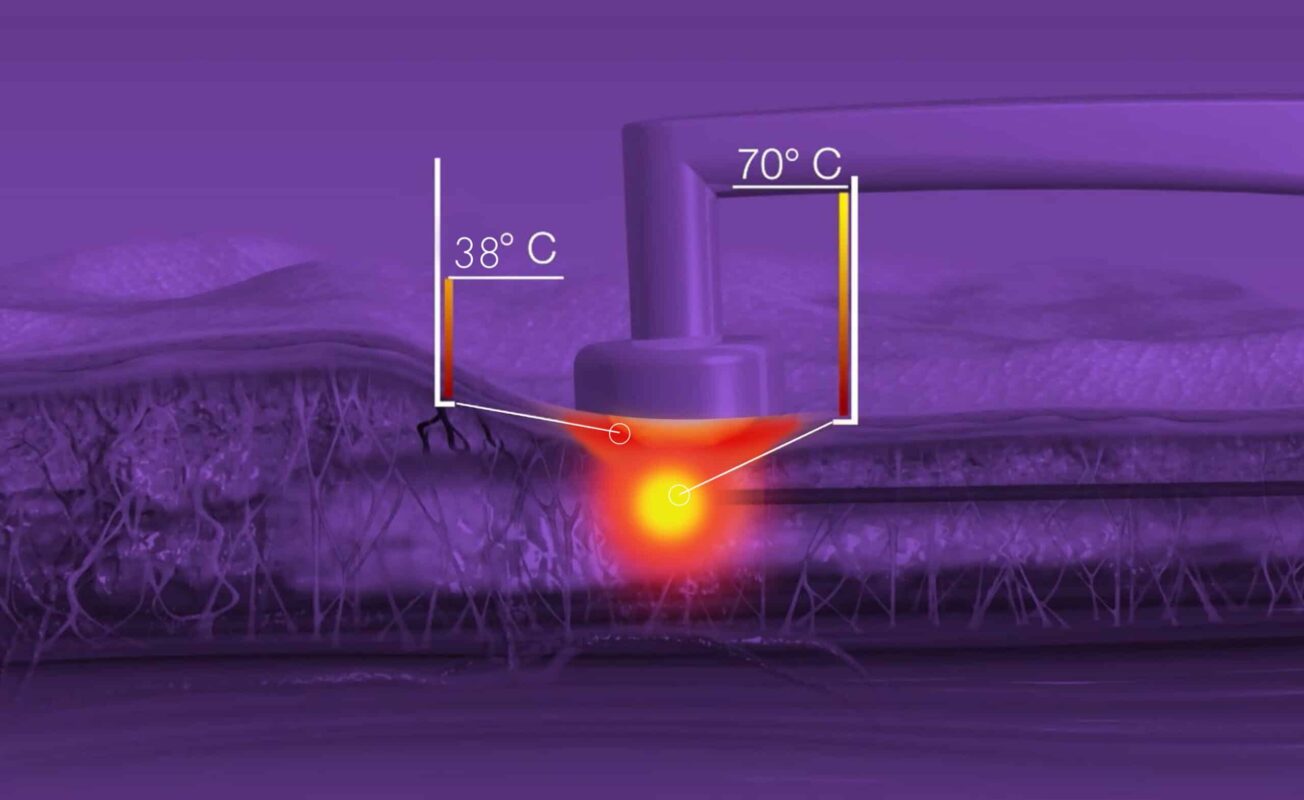

Bodytite utiliza la tecnología patentada RFAL (Lipólisis Asistida por Radiofrecuencia) A.C.E, la única aprobada por la Food And Drug Administration (FDA) con control doble de temperatura.

A diferencia de otros sistemas, esta tecnología permite aplicar la radiofrecuencia bajo la piel, consiguiendo hacer llegar la energía a más profundidad.

Mediante una lipólisis interna, externa y superior, la remodelación corporal 3D que ofrece Bodytite consigue una contracción tridimensional de la dermis, el tejido conectivo subcutáneo y el tejido graso profundo. Su efecto consigue unos resultados que hasta ahora sólo se conseguían con una liposucción tradicional.

El tratamiento se realiza utilizando una cánula con dos partes: la más fina se introduce en la piel a través de una incisión mínima, mientras que la más gruesa se coloca encima de la piel.

Ambas cánulas cuentan con un electrodo situado en el extremo proximal a través del cual, y de forma bidireccional, se transmiten las ondas de radiofrecuencia produciendo un calentamiento bipolar, rápido y uniforme de la grasa hasta licuarla.